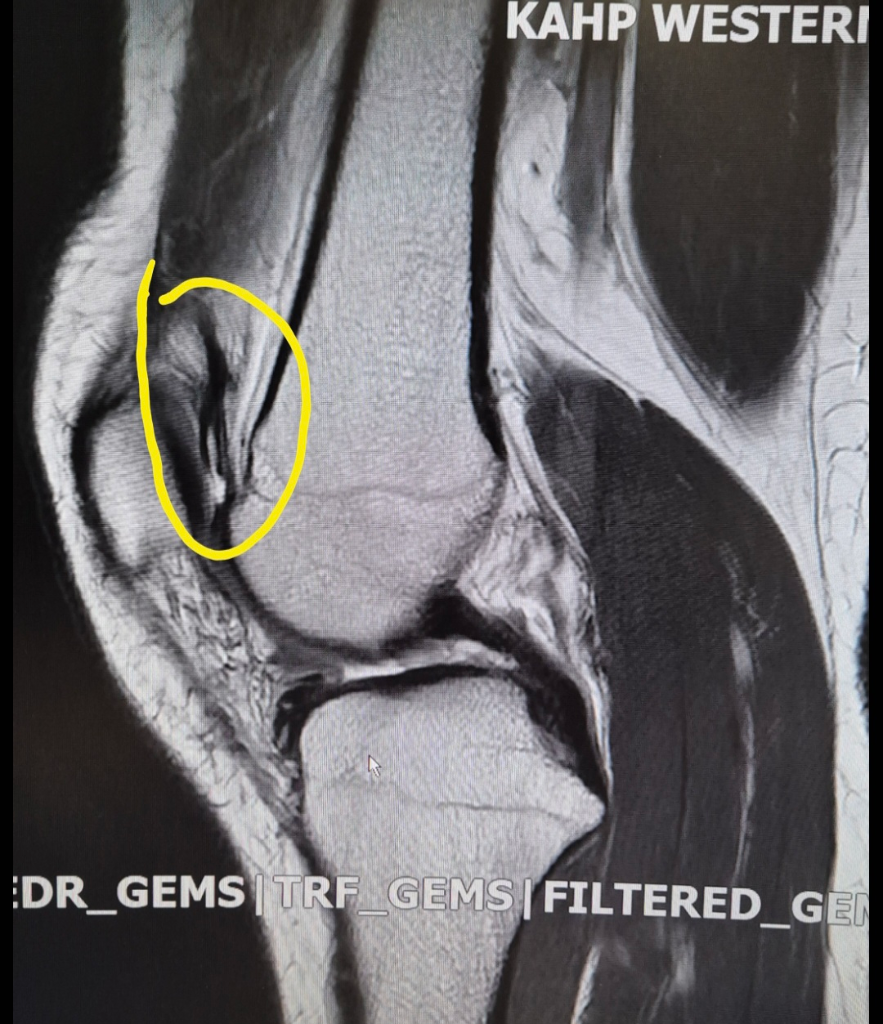

무릎 mri 요 구조물은 뭔가요ㅜ?

와이드스쿼트자세에서 무릎을 바깥으로 돌리다가 안에 찢어지는 소리? 느낌이 나면서 다쳐서 무릎 mri 를 찍게됐는데 저 검은줄은 뭘까요ㅜ? 다른 무릎 mri 를 보면 저런 구조물은 없는거같아서요...

무릎 mri에서 보이는 검은 줄은 대부분 연골, 인대, 발월상연골 등 밀도가 높은 구조물 때문입니다. 와이드 스쿼트 중 찢어지는 느낌이 났다면 반월상연골 손상이나 인대 미세손상 가능성이 있습니다 다른 mri와 차이가 있어 보이는 것은 촬영각도나 절단면에 따라 구조물이 다르게 나타날 수 있습니다!